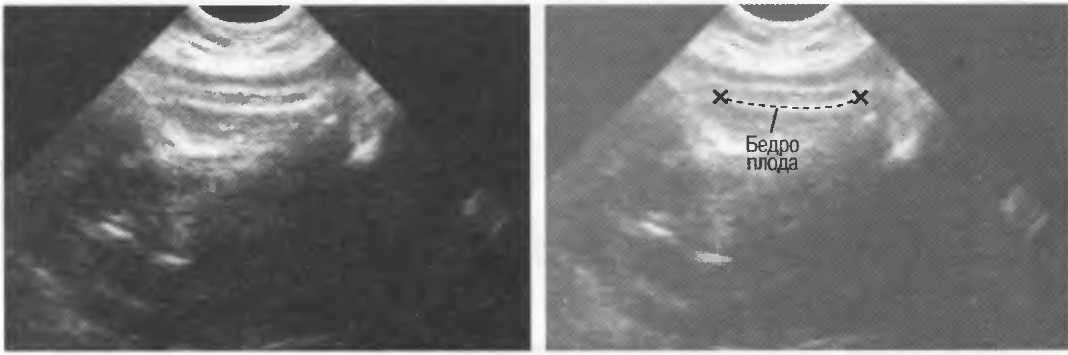

Неполное изображение

Артефакты в результате неполного изображения являются источником тревоги у исследователя, так как получается изображение только той части структуры, которая находится в плоскости сканирования. Так, при исследовании плода может визуализироваться только часть кости, а остальная часть может не попадать в плоскость. В результате, кость может выглядеть неполной или короче, чем она есть на самом деле (рис. 21а,б).

Рис.21а. Неполное изображение кости плода.

Рис.21б. В данном случае кость плода визуализируется полностью.